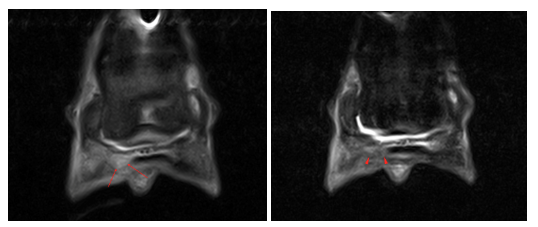

The mare continued to make good clinical progress and remained comfortable. Her bloodwork was normal. There was very little drainage from the foot. Encouragingly, there was a reduction in fluid signal in the deep digital flexor tendon as shown on the below STIR frontal images (previous study to the left and recent to the right).

There was partial resolution of the fluid signal in the solar tissues (red arrowheads) and decreasing signal within the lateral aspect of the DDFT (red arrows) on the T2 FSE transverse image (previous to the left and recent to the right)